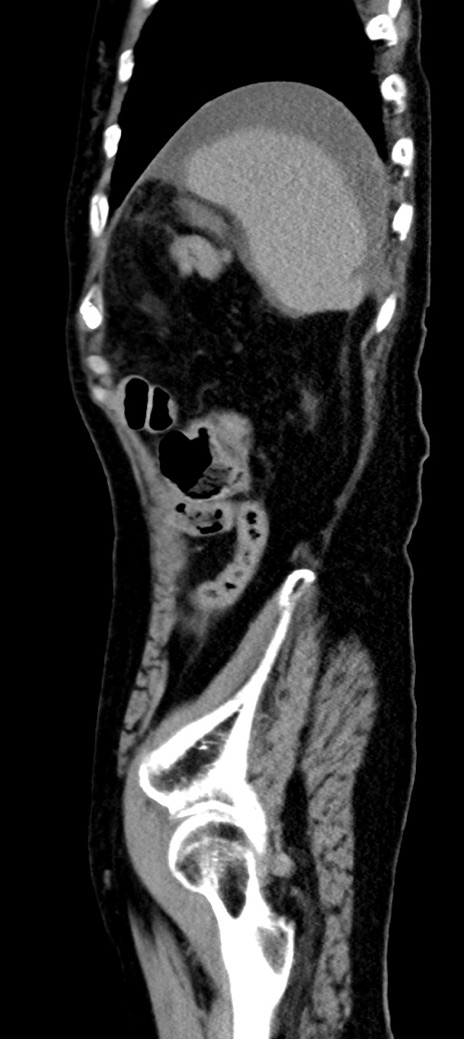

症例40(矢状断像)他院1日前

【症例】90歳代女性

【主訴】腹痛・嘔吐

【現病歴】 食欲低下、嘔吐があり昨日他院受診。肺炎と診断され入院となる。入院後より腹部全体に圧痛あり。胃管留置され経過みていたが、症状持続するため、

当院転院となる。

【既往歴】胸椎圧迫骨折、胆石症

【身体所見】腹部:中央に激痛あり、圧痛あり、反跳痛不明

【データ】WBC 17100、CRP 18.82